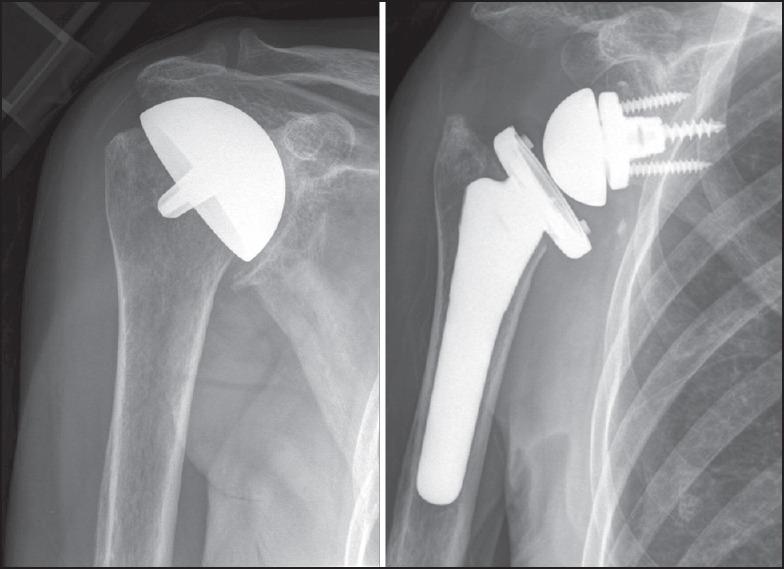

MATERIALS AND METHODS

All patients were revised to stemmed arthroplasties, including one hemiarthroplasty, two reverse, and eight anatomic total shoulder arthroplasties at a mean 33 months after primary resurfacing (range 10-131 months). A deltopectoral approach was used in seven patients; four patients required an anteromedial approach due to severe scarring. Subscapularis attenuation was found in four cases, two of which required reverse total shoulder arthroplasty. Bone grafting was required in one glenoid and three humeri.

材料与方法

所有患者均翻修为带柄关节成形术,包括1例半关节成形术、2例反向和8例解剖型全肩关节成形术,初次表面置换后平均33个月(范围10 - 131个月)。7例患者采用三角肌胸大肌入路;4例患者因严重瘢痕需要采用前内侧入路。4例发现肩胛下肌减弱,其中2例需要行反向全肩关节成形术。1例关节盂和3例肱骨需要植骨。